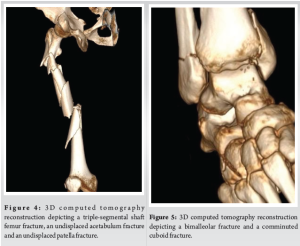

A 34-year-old male was brought to our emergency department following a high-energy road traffic accident. The patient’s complaints included severe pain, swelling, and an inability to bear weight on his left lower limb. Upon clinical examination, the left thigh had considerable soft tissue swelling and localised tenderness. Despite having stable vital signs, he appeared distressed due to the pain and swelling. X-rays of the left thigh revealed a triple-segmental shaft femur fracture (Fig. 1). This is an uncommon pattern–the femur is divided into five segments. Additional imaging revealed a bimalleolar fracture, a comminuted cuboid fracture, an undisplaced acetabulum fracture, and an undisplaced patella fracture (Fig. 2).

In this case, a computed tomography (CT) topogram/scout view/scanogram was utilised to accurately assess the femoral anatomy and determine the appropriate size for the intramedullary nail [5-7]. We measured the diameter and length of the femoral canal, ensuring precise selection of the nail size (Fig. 3). A 3D CT reconstruction was also done to aid surgical planning (Fig. 4 and 5).